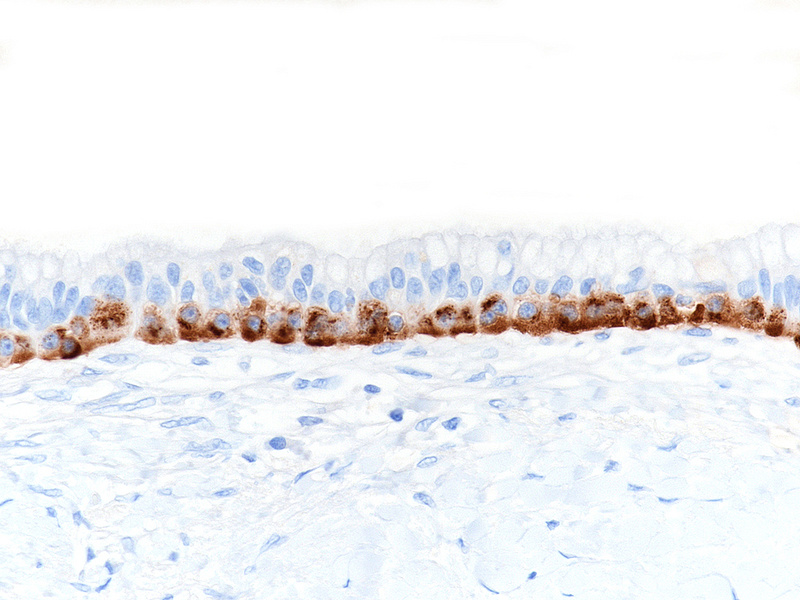

Upon magnetic resonance imaging (MRI) the pancreas contains several cystic lesions plus one partly solid, partly cystic lesion with a maximum diameter of 15 mm within the body. This lesion shows a biphasic pattern (Panel A). There are cysts lined by mucin-producing columnar cells with low grade dysplasia, consistent with a diagnosis of intraductal papillary mucinous neoplasm (IPMN). Other parts show a mainly solid, but also pseudoglandular growth of cuboidal cells with eosinophilic granular cytoplasm and centrally placed nuclei with “salt and pepper” chromatin and small nucleoli (Panels B-C). Mitoses are not detected. The two components merge with each other (Panel D), and in some foci the eosinophil granular cells underline the columnar cells (Panel E). The solid tumour component is strongly positive for synaptophysin (Panel F) and chromogranin A (Panel G), as are the underlining cells within the cystic component (Panel H). The Ki67 proliferation rate is low in the columnar epithelium (Panel I) and even lower (4%) in the solid component (Panel J). It is of note that the cells within the solid component express glucagon, while the cyst-lining mucus-producing cells are negative (Panels K-L).